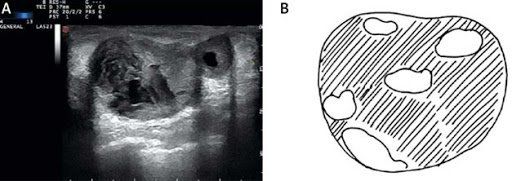

Siêu âm u nang tuyến vú thường có đặc điểm như sau:

- Hình bầu dục hoặc hình tròn

- Không dội âm (không có tiếng vọng bên trong).

- Giới hạn rõ.

- Tăng cường âm thanh phía sau

- Thành nhẵn

- Vôi hóa ngoại vi.